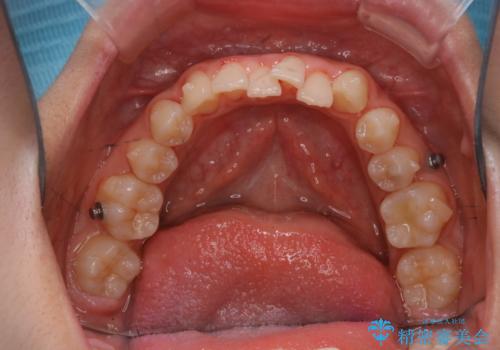

また、矯正で歯の移動があると今までなかったところに隙間が出てきたり、ガタつきが解消されてきたりすることで、お口の中の環境が変わります。

矯正治療中も清潔な口腔内を保つことは、とても大切です。そのため、定期的に専門的な機械・材料を使用したProfessinnalcleaning(pmtc)を行うことがおススメです。